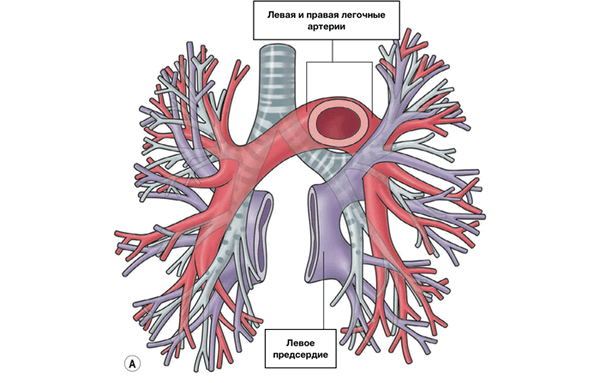

Легочный ствол (truncus pulmonalis) диаметром 30 мм выходит из правого желудочка сердца, от которого он отграничен своим клапаном. Начало легочного ствола и соответственно его отверстие проецируются на переднюю грудную стенку над местом прикрепления хряща III левого ребра к грудине. Легочный ствол расположен кпереди от остальных крупных сосудов основания сердца (аорты и верхней полой вены). Справа и позади него находится восходящая часть аорты, а слева прилежит левое ушко сердца. Легочный ствол, находящийся в перикардиальной полости, направляется впереди аорты влево и кзади и на уровне IV грудного позвонка (хряща II левого ребра) делится на правую и левую легочные артерии. Это место называется бифуркацией легочного ствола (bifurcаtio tninci pulmonalis). Между бифуркацией легочного ствола и дугой аорты расположена короткая артериальная связка(ligamentum arteriosum), представляющая собой заросший артериальный (боталлов) проток (ductus arteriosus).

Левая легочная артерия (a.pulmonаlis sinistra) короче и тоньше правой, проходит от бифуркации легочного ствола по кратчайшему пути к воротам левого легкого в поперечном направлении впереди нисходящей части аорты и левого бронха. На своем пути артерия перекрещивает левый главный бронх, а в воротах легкого располагается над ним. Соответственно двум долям левого легкого легочная артерия делится на две ветви. Одна из них распадается на сегментарные ветви в пределах верхней доли, вторая — базальная часть — своими ветвями кровоснабжает сегменты нижней доли левого легкого.

Из капилляров легкого начинаются венулы, которые сливаются в более крупные вены и в каждом легком формируют по две легочные вены.

Из двух правых легочных вен больший диаметр имеет верхняя, так как по ней оттекает кровь от двух долей правого легкого (верхней и средней). Из двух левых легочных вен больший диаметр имеет нижняя вена. В воротах правого и левого легких легочные вены занимают их нижнюю часть. В задней верхней части корня правого легкого расположен главный правый бронх, кпереди и книзу от него — правая легочная артерия.

У левого легкого сверху находится легочная артерия, кзади и книзу от нее — левый главный бронх. У правого легкого легочные вены лежат ниже артерии, следуют почти горизонтально и на своем пути к сердцу располагаются позади верхней полой вены, правого предсердия и восходящей части аорты. Обе левые легочные вены, которые несколько короче правых, находятся под левым главным бронхом и направляются к сердцу также в поперечном направлении, кпереди от нисходящей части аорты. Правые и левые легочные вены, прободая перикард, впадают в левое предсердие (их конечные отделы покрыты эпикардом).